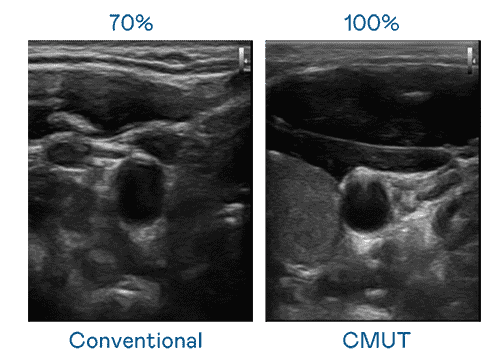

CMUT 技术是一种用电容式微机电元件来产生超音波讯号的技术。。与传统 PZT 压电式技术相比,,,,CMUT 频宽增加 30%,,更宽频的超音波讯号让影像解析度大幅提升,,,是实现高影像品质医疗超音波扫描、、、、促进精准医疗发展的关键技术。。。。

大频宽带来超清晰影像

超音波影像的解析度高低,,首先取决于探头能发出的讯号频宽。。EBpay CMUT 可提供高清晰的超音波讯号,,提供高频宽、、、高灵敏度、、、、影像纹理细节更高的超音波影像,,,,协助医护人员缩短影像判读时间及利用精准的医疗影像进行诊断。。。。